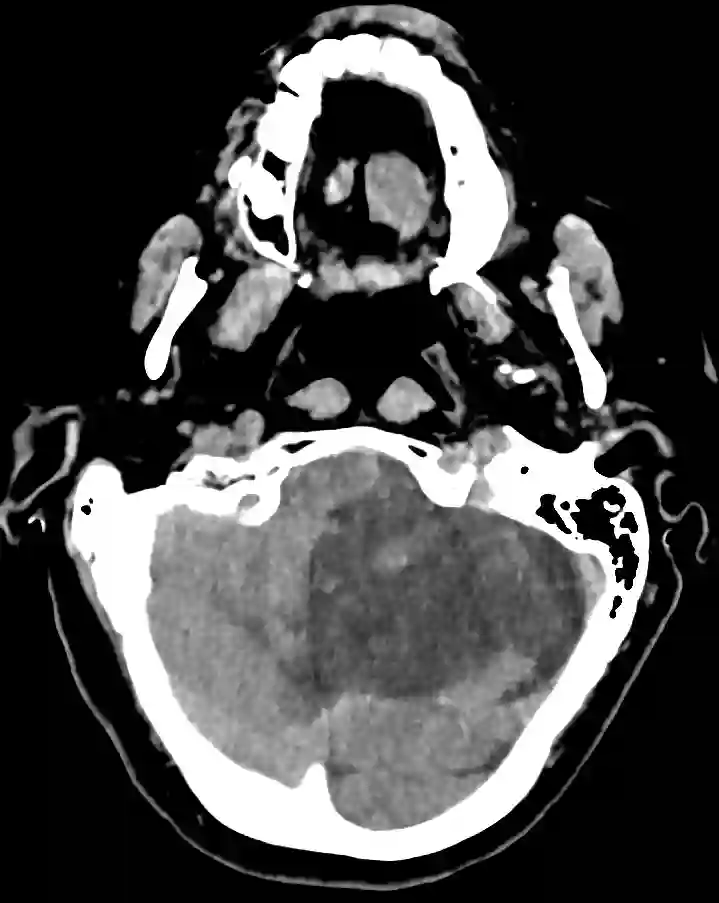

Linksseitiger PICA Infarkt im axialen CT Bild

Axiale Darstellung eines PICA Infarkts im CT.